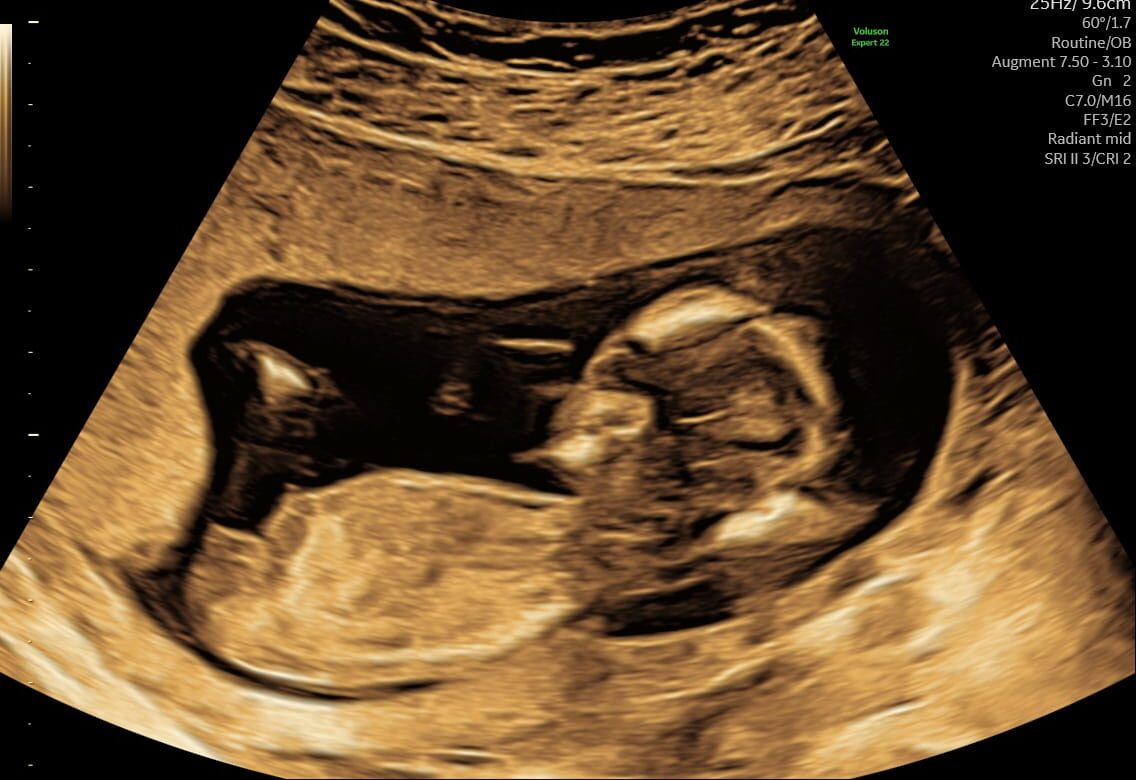

Kan jeg få tvillinger kønsscannet?

Ja du kan bestemt få dine tvillingers køn scannet, det koster bare lidt ekstra. Men du får stadig de samme fordele, både scanningsbilleder og video kan du få overført til din telefon.

Venter du tvillinger, ja så er der nok at se til og bruge pengene på, vi sætter dobbelt så lang tid af, men det koster kun lidt ekstra. Vi tager 895,- for en kønsscanning af tvillinger.